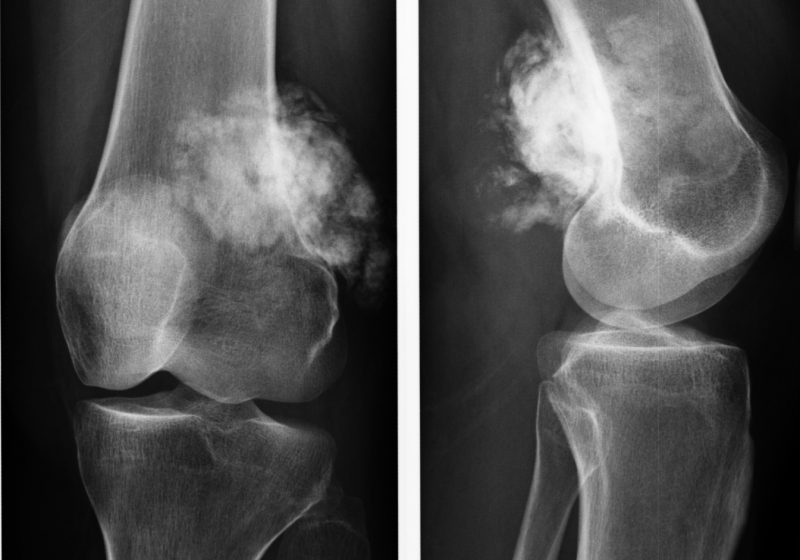

Рентгенологическая картина остеогенной саркомы кости - 98 фото